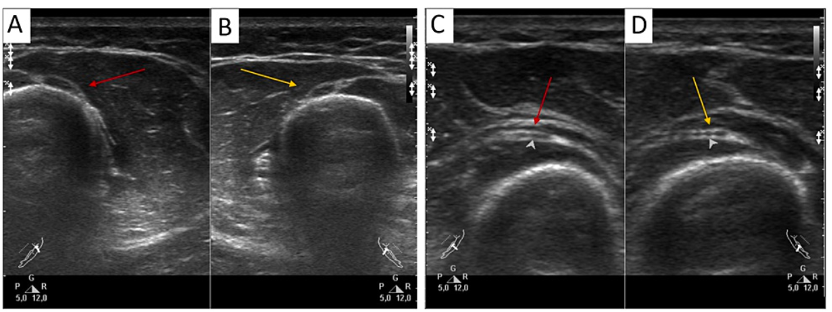

在受影响的个体中,有五人寻求了医疗救助。对其中两名患者(病例1和病例2)进行的神经传导研究(NCS)分析显示,上臂桡神经是病人最常受影响的神经,90.0%的患者和81.3%的受伤涉及此神经。通常,绳索位于上臂中段,以保证水平或侧面悬挂,个体的身体分别面向下方或侧面。手通常以盒子结构(如图1A所示)被系在一起。受影响的个体经常报告背侧手腕麻木以及手腕和手指伸肌不同程度的虚弱感,范围从完全麻痹到中度虚弱。此外,手背侧的感觉丧失也常被提及。

图1:图示了上臂中段桡神经受损(病例1)的完全水平悬挂(A)以及腋神经受伤(病例10)(B)。

高分辨率超声检查显示受影响侧的桡神经具有清晰、平滑的轮廓,异质性的束内部结构,以及正常的回声(图3A、3B)。受影响神经的横截面积在正常范围内,为0.10平方厘米(参考范围:0.065-0.116平方厘米)。值得注意的是,这个值高于均值(0.087 ± 0.009平方厘米),且大于对侧未受影响神经的横截面积(0.081平方厘米)。在肘关节水平,两侧神经的横截面积没有差异(图3C、3D)。

图3:所呈现的横断声图描述了螺旋沟处受影响(左侧,红色箭头)和未受影响(右侧,橙色箭头)的桡神经,以及在旋前肌处(C、D)的桡神经深支。高分辨率超声检查显示,在螺旋沟处,受影响侧桡神经的横截面积相较于对侧略微增大(A)。